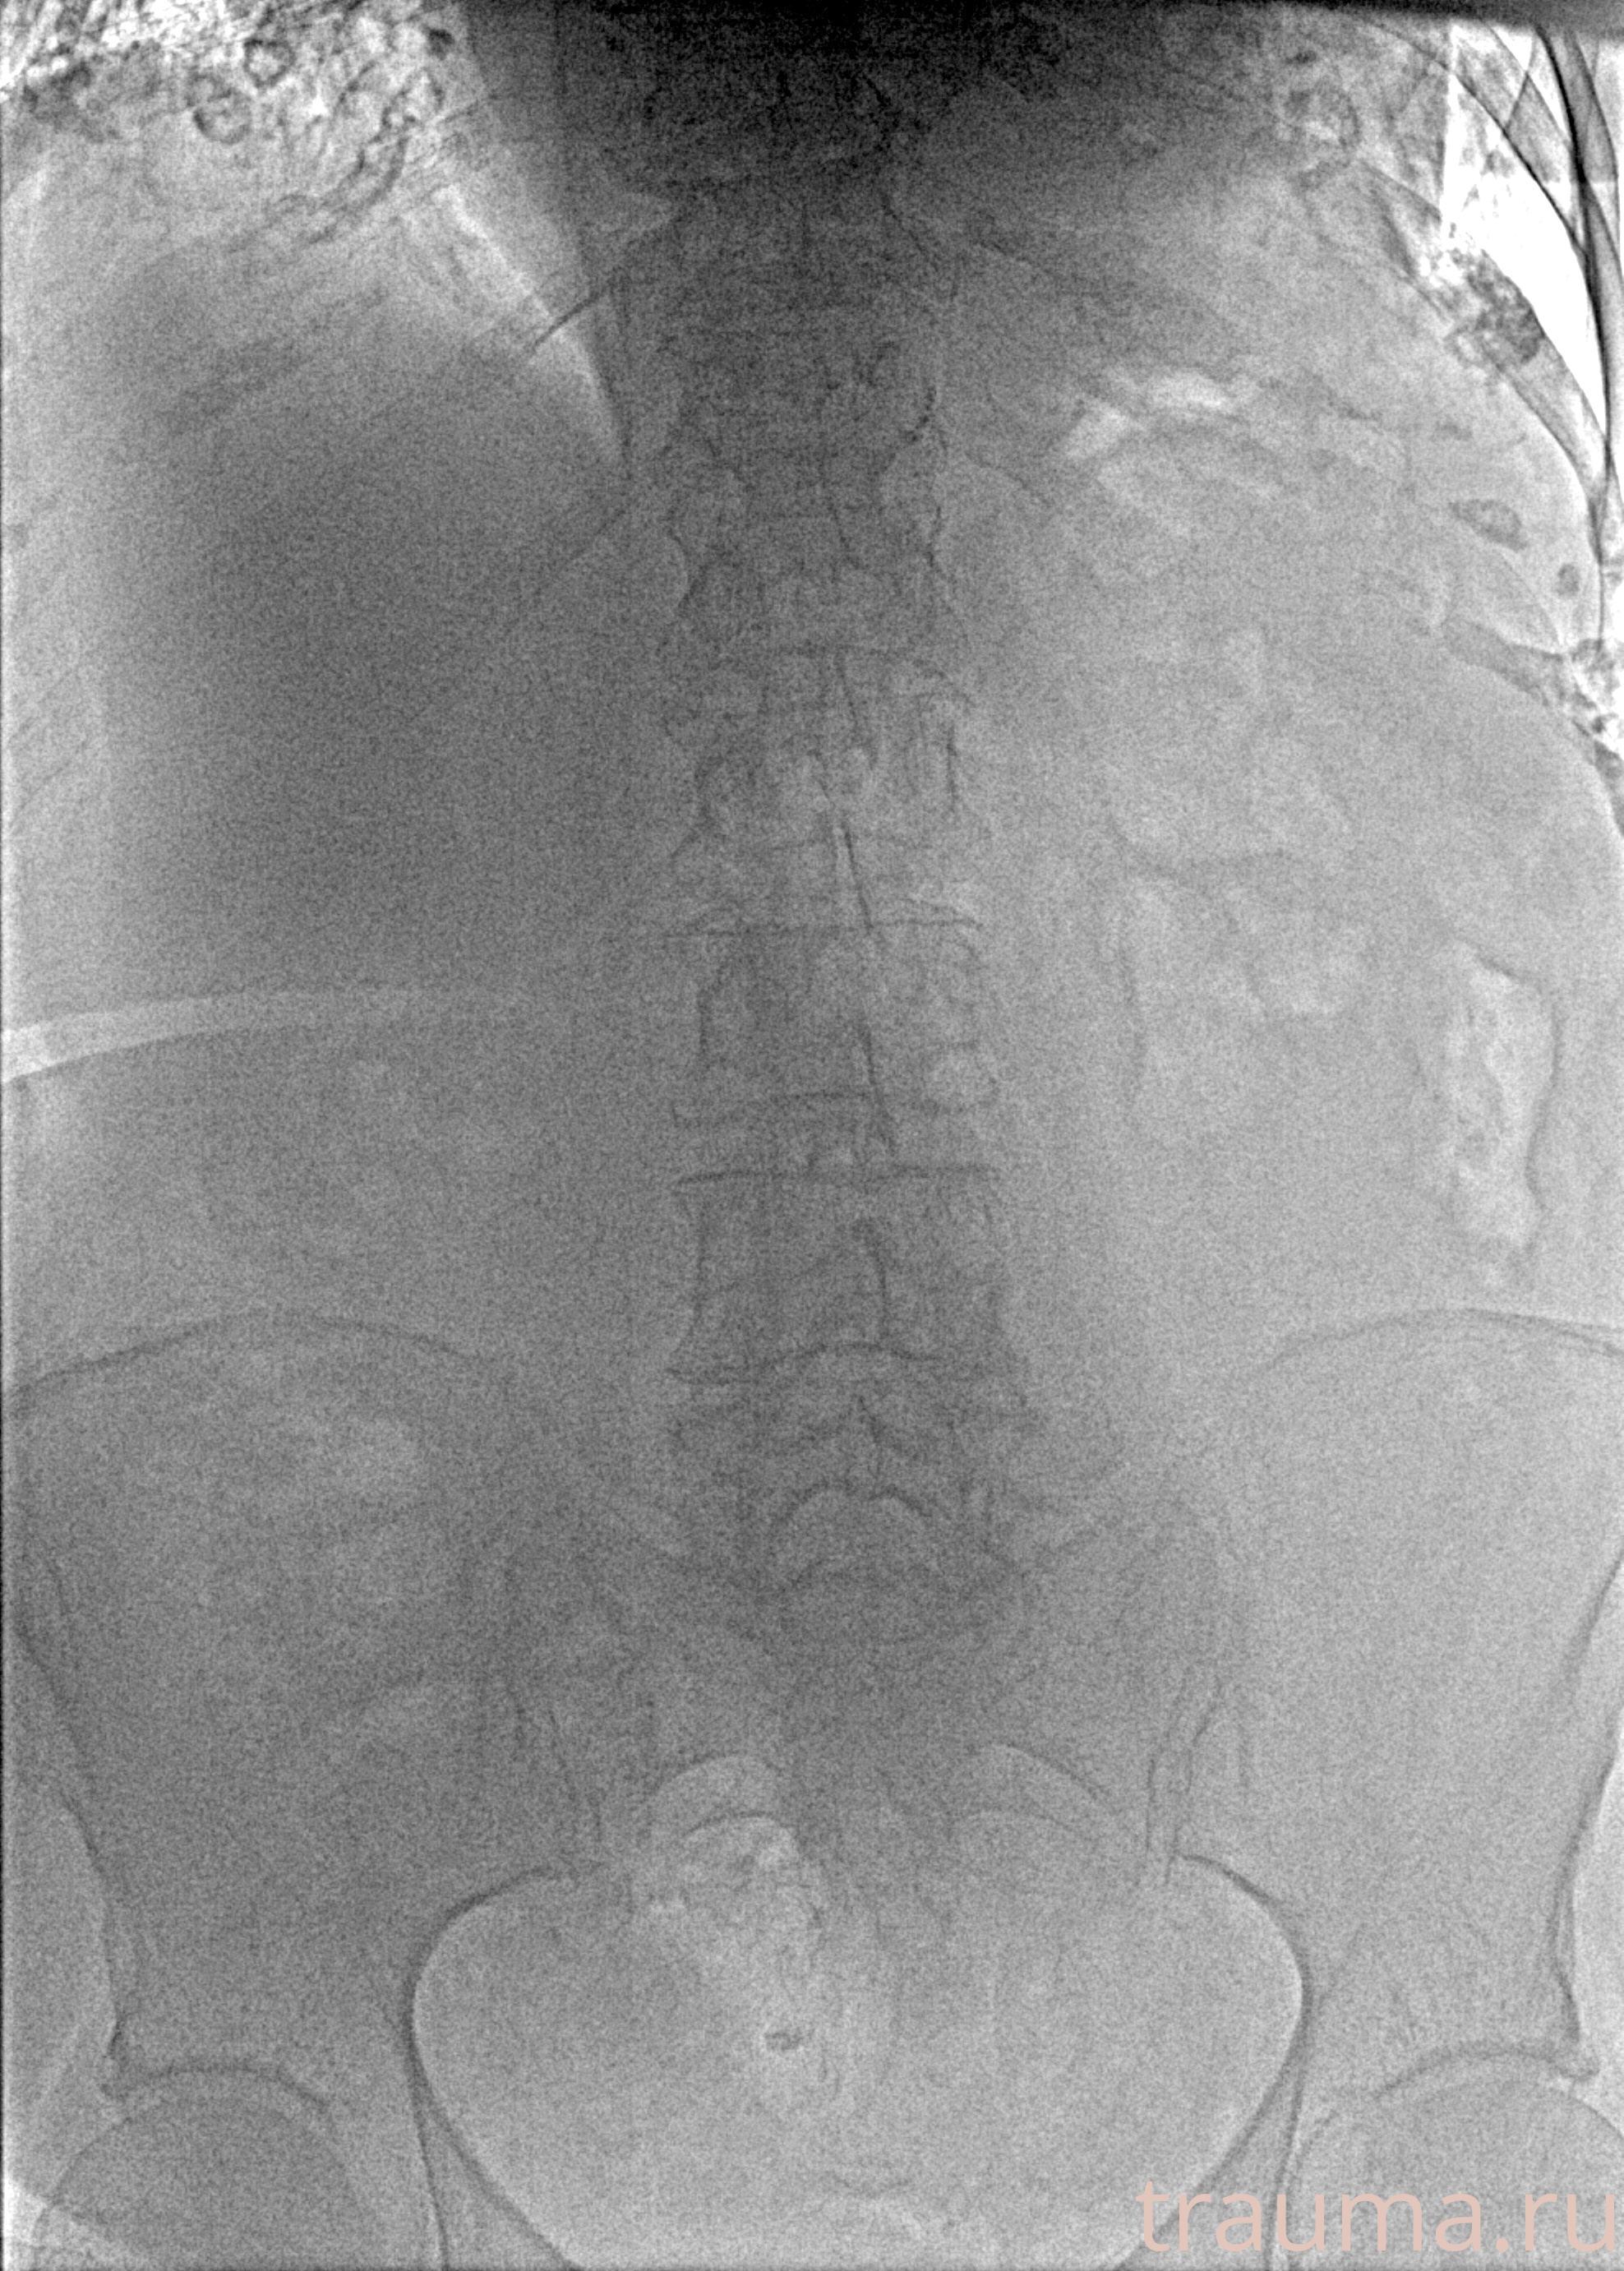

Рентгенограммы

Рентген на дому: по вашему адресу приезжает врач-рентгенолог, травматолог-ортопед с мобильным рентгеновским аппаратом, проводит диагностику травмы или заболевания, делает необходимые рентгенограммы, дает рекомендации по дальнейшему лечению. Получить качественные снимки в домашних условиях возможно благодаря уникальной методике, разработанной МосРентген Центром для института  Склифосовского